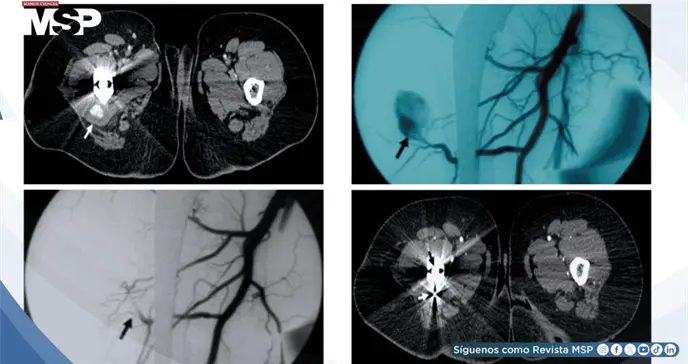

La tomografía computarizada posterior precisó las características de la lesión: un pseudoaneurisma de 14 × 22 mm que se originaba específicamente en una rama perforante distal de la arteria femoral profunda derecha.

Se realizó una arteriografía mediante acceso retrógrado por la arteria femoral izquierda, confirmando la presencia y características del pseudoaneurisma.

El procedimiento terapéutico consistió en el cateterismo selectivo de la rama perforante comprometida utilizando un microcatéter especializado. Se logró la embolización exitosa mediante la colocación estratégica de bobinas de platino de 2 y 3 mm, posicionadas tanto distal como proximalmente al cuello del pseudoaneurisma. La angiografía de control inmediata demostró la exclusión completa de la lesión, sin evidencia de flujo residual hacia el saco aneurismático.